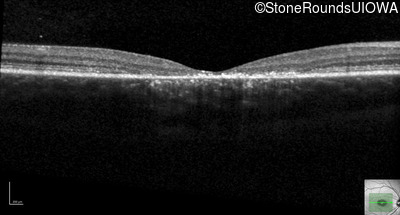

Optical Coherence Tomography - Left - 20/125 sc

Exemplar / OCT Stack